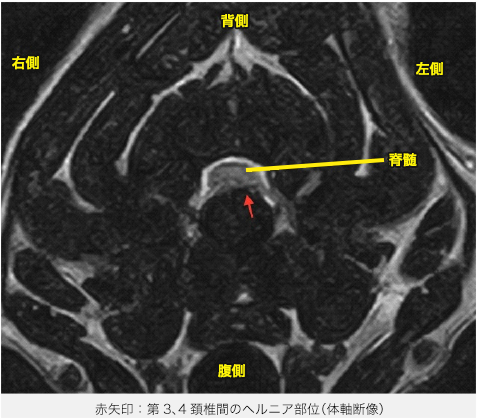

MRI検査では脳炎の所見は認められず、頚部において第3、4頚椎間の椎間板がヘルニアを起こし、左腹側から脊髄を圧迫していることが分かりました。以上のことから第3、4頚椎間の椎間板ヘルニアと診断しました。